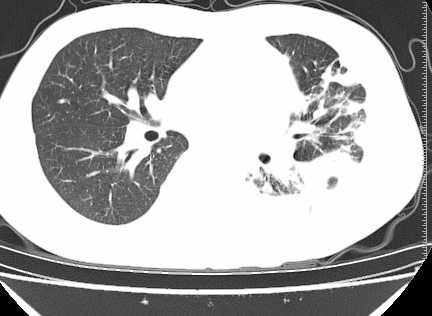

年龄?左侧胸腔中量积液,左下肺见有较多斑片状和大片状影,伴有支气管充气征,考虑:1、左下肺炎;2、结核。肿瘤可以基本排除。

考虑:1、左下肺结核左侧胸腔中量积液,心包积液纵隔肿大淋巴结.

考虑:1、左侧中量胸腔积液伴左肺下叶肺膨胀不全、炎症。

左下肺见有较多斑片状和大片状影,支气管通畅,左侧胸腔积液,考虑:左下肺炎伴胸腔积液

左侧中量胸腔积液伴左肺下叶肺膨胀不全、上肺外围多个小囊样腺泡样病灶。考虑化脓炎症。

患者刺激性干嗽,无咯血,伴心悸,低热,夜间无明显盗汗,消瘦明显,左侧中量胸腔积液伴左肺下叶肺膨胀不全、上肺外围多个小斑片病灶。考虑肺结核可能性大。

左肺舌叶及下叶见斑片状,大片状高密度影并相应处胸膜及心包不规则增厚,左肺下叶膨胀不全。右肺未见异常,双肺段以上支气管通畅。纵隔左移,其内未见明显肿大淋巴结。左侧胸腔积液。

1.考虑:左肺化脓性炎症。2.左侧胸腔积液(中等量)。3.心包炎症。